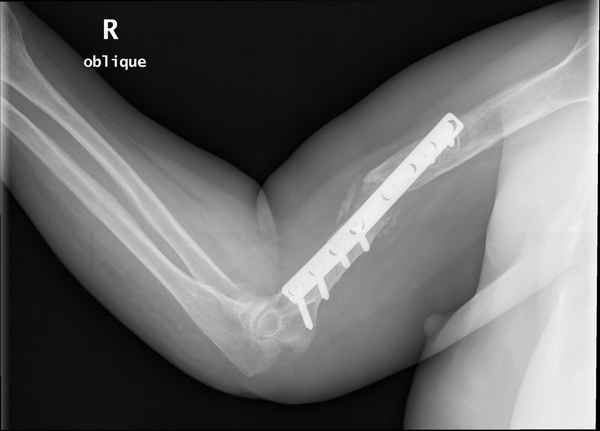

Больная 48 лет, медсестра-массажист, перелом плеча 7 лет назад, оперирована 4-кратно и безуспешно

Больная 48 лет, медсестра. Травма получена 7 лет назад, оперирована первично в Турции - остеосинтез пластиной - несращение - реостеосинтез стержнем там же через год (обычным, с выстоянеием его в полость плеча) - несращение - поступила к нам впервые в марте 2008 года - удаление стержня, реостеосинтез пластиной и костная пластика, в течение 2 лет лизис кости вокруг винтов, смещение фиксатора, в марте 2010 - удаление пластины, реостеосинтез интрамедуллярным стержнем с блокированием (рассверливание + костная пластика). В динамике - вновь лизис в области перелома, нестабильность дистальных блокирующих винтов.

Клинически фиксация пока действительно стабильна, но на рентгенограммах резорбция кости в области дистальных блокирующих винтов и миграция одного из них.